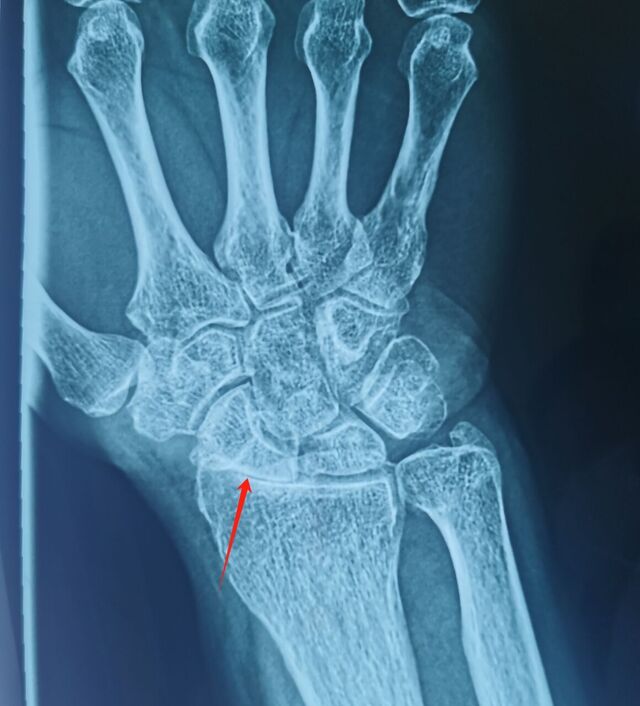

腕关节骨性关节炎

SLAC分期:

I期,舟骨窝局限性关节炎始于桡骨茎突

II期,发展到近端舟骨窝

III期,进而出现头月关节炎

IV期,全腕关节炎

该病例需要做CT重建

判断腕关节骨性关节炎分期

根据分期决定具体术式